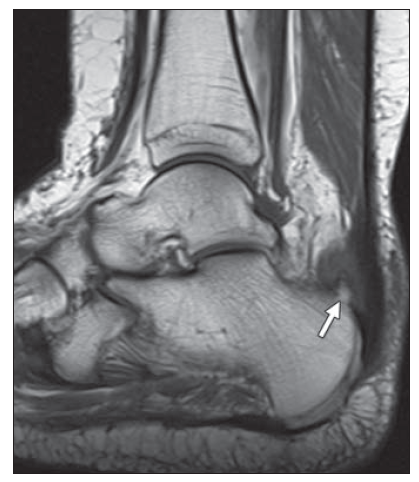

临床表现:跟腱止点部位疼痛不适,运动时疼痛加剧;渐进性病程,后期逐渐表现为任何活动都可引发疼痛。

体检:跟骨结节后方肿胀、压痛;踝关节主动背伸受限和提踵力量减弱;Silverskold试验可为阳性。

止点变性和钙化严重导致彻底清理后跟腱止点缺损超过50%时需要行跟腱止点重建。